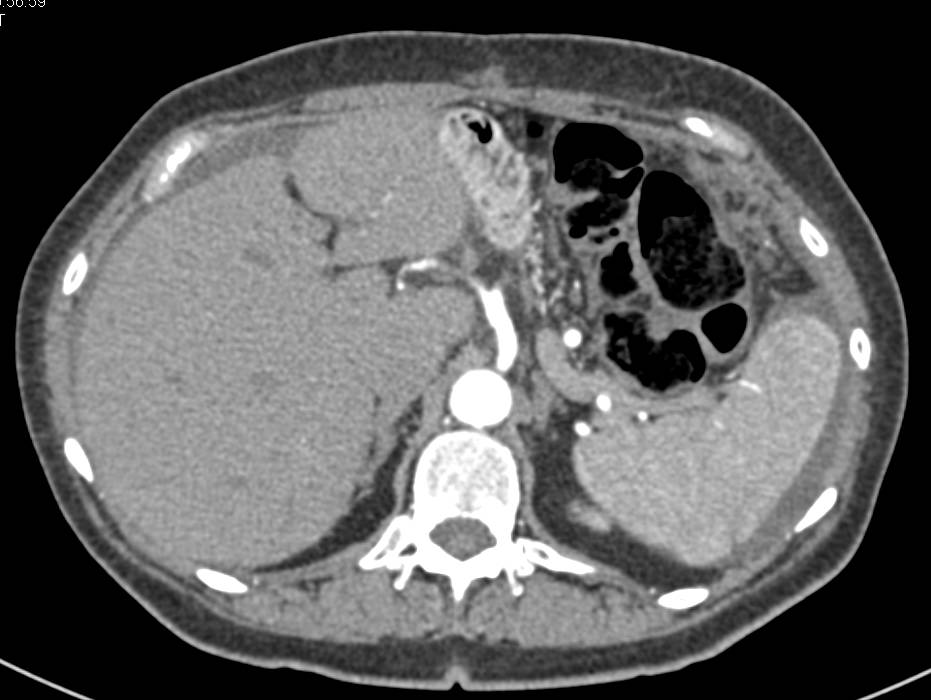

Lymphoepithelial Cyst of the Pancreas